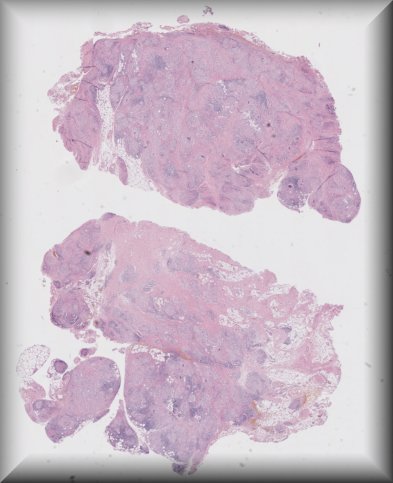

Luciane Dreher Irion (Manchester): 53-year-old male with a 6 month history of proptosis and right subconjunctival lump extending to temporal orbit. Incisional episcleral biopsy performed. |